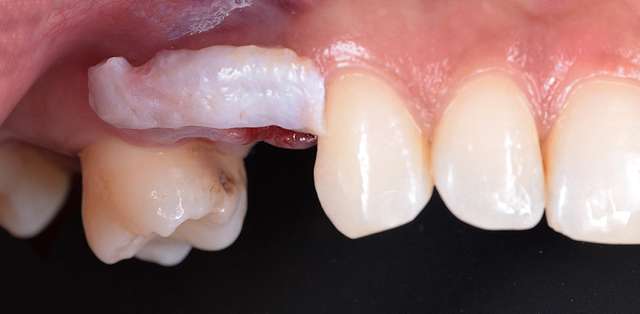

Guided surgery, for one, facilitates an ideal pre-planned position, in relation to available bone, and even more important, in relation to the future implant supported crown. Guided surgery translates into increased precision, which means safer surgeries, reduced surgery time, and reduced trauma. Also the focus of these types of treatments is shifted towards tissue reconstruction, which on the long run, has a far greater impact esthetically and biologically. Tissue stability means implant longevity. This case is a relevant example for this type of approach towards implant dentistry.